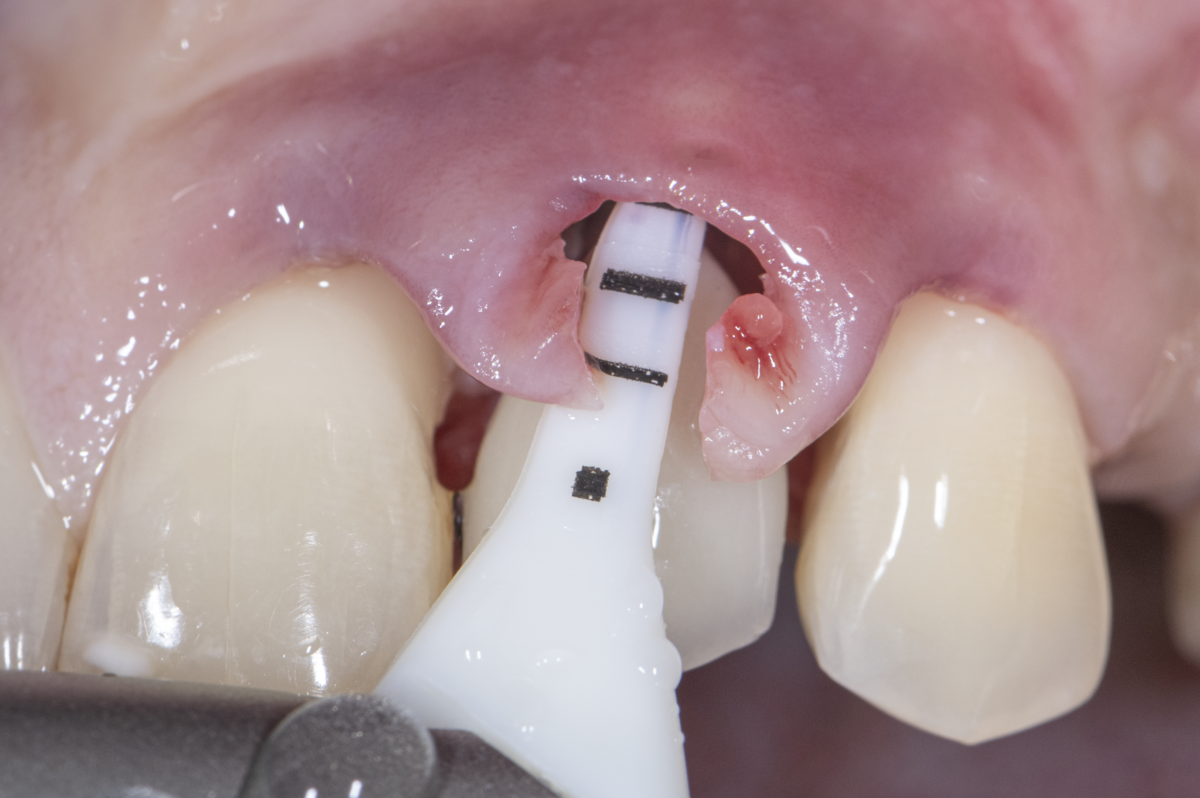

In this respect, a microsurgical approach with the use of optical magnification, microsurgical instruments, and microsurgical suture materials has scientifically proven advantages, and is today even considered indispensable from a clinical point of view.

The benefits of a precise and atraumatic treatment approach—which include significantly reduced morbidity, better clinical outcomes, and higher patient satisfaction regarding the procedure, as well as aesthetic treatment results such as scar-free healing, natural appearance, and harmonious tissue transitions—are becoming increasingly evident (Figure 3).